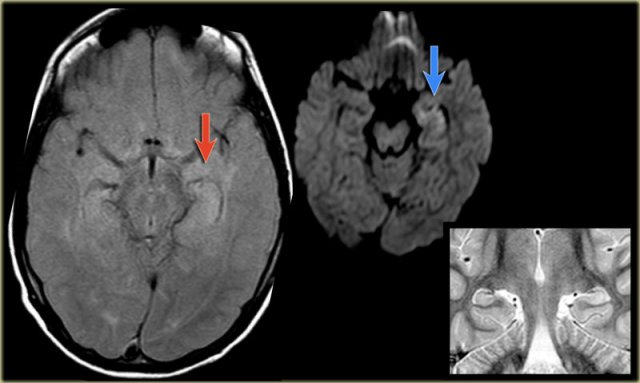

The coronal T2WI and FLAIR images show right-sided mesial temporal sclerosis.

Notice the volume loss, which indicates atrophy and causes secondary enlargement of the temporal horn of the lateral ventricle.

The high signal in the hippocamous reflects gliosis.

The images show mesial temporal sclerosis with a hyperintense and shrunken hippocampus (red arrows), and secondary enlargement of the left temporal horn of the left laterale ventricle.

Also notice associated subcortical hyperintensity in the left temporal lobe indicating focal cortical dysplasia.

35-year-old patient with refractory temporal lobe epilepsy.

MR shows subtle hyperintensity of the left hippocampus on the axial FLAIR (blue arrow) and atrophy of the left hippocampus on coronal images (yellow arrow).

The patient was succesfully treated with amygdalo-hippocampectomy on the left.